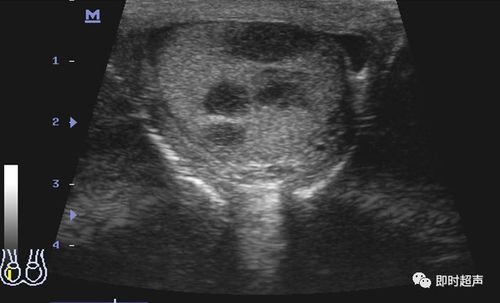

阴囊及其内容物的超声诊断_睾丸